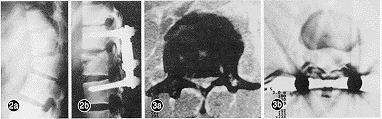

所有病例术后均摄X线片及行CT复查(图2、3,插Ⅳ)。X线片示骨折椎体高度全部恢复42例,基本恢复7例,过度撑开2例,1例无变化。有骨折块突入椎管的38例中,全部复位者31例,突出小于3mm者4例,大于3mm者3例。术后CT示椎管矢状径小于10mm者8例。52例除3例失访外,其余49例均获随访。多数患者术后1周即能在床上坐起,2周能下地站立。神经功能恢复按Frankel分级评定,28例不完全性截瘫者均有1~3级恢复,其中21例下肢肌力达V级,有5例小便功能恢复欠佳。5例全瘫者除1例外均有1~2级恢复。

图2 L1骨折AF固定术前后X光片(a 术前,b 术后) 图3 L1爆裂骨折AF固定前后椎管情况(a 术前,b 术后)